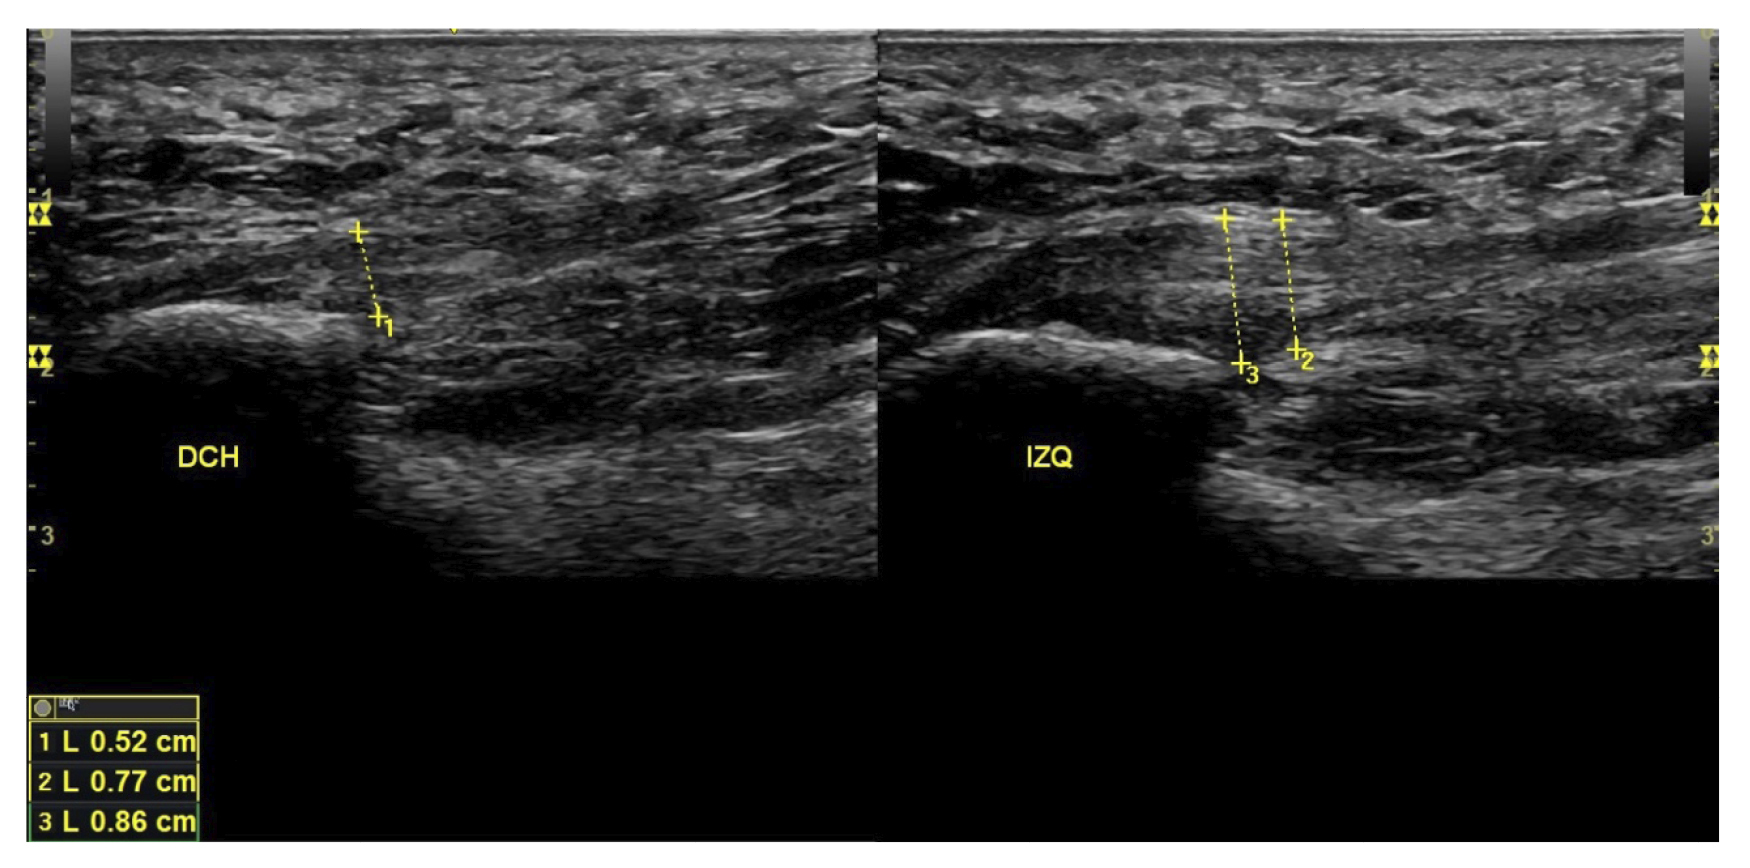

Variables utilizadas

A todos los pacientes se les realizó una evaluación clínica y una evaluación ecográfica. La evaluación clínica se basó en una escala analógica visual (EVA) (13) (0-10) y el índice de función del pie (FFI) (14,15), que evalúa la función en una escala de 0 a 100. También se clasificó a los sujetos como sedentarios, activos o deportistas en función a su actividad física diaria, así como si era la primera vez que aparecía la enfermedad, era una recidiva o era crónica(16). También se evaluó el sexo, el peso y la talla, la presencia de vascularización en la fascia plantar visualizada con ecografía en el momento de la evaluación inicial y la forma biconvexa(17) o aplanada de la fascia plantar (Figura 1).

El diagnóstico se estableció en base a los síntomas y se confirmó mediante ecografía con equipo de alta resolución (Alpinion Ecube 9, ALPINION MEDICAL SYSTEMS Co., Ltd., República de Korea) con transductor lineal de 6 a 12 MHz (Figuras 2 y 3).

Figura 3. Área de medición del grosor de la fascia plantar. La línea punteada corresponde con la medición del grosor.